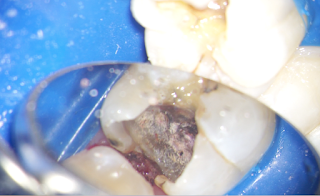

例えば、この銀歯の中がどうなっているかですが。

銀歯を外した直後です。

その下の保護材をとって行きます。

赤いところが虫歯で汚染された歯質です。

かなり深い位置まで虫歯が進行しています。

更に虫歯をとっていくと、歯茎の下の深い位置まで進行しています。

まだ残っているので除去を続けます。

虫歯の除去後に、神経保護のセメントを置いた状態です。